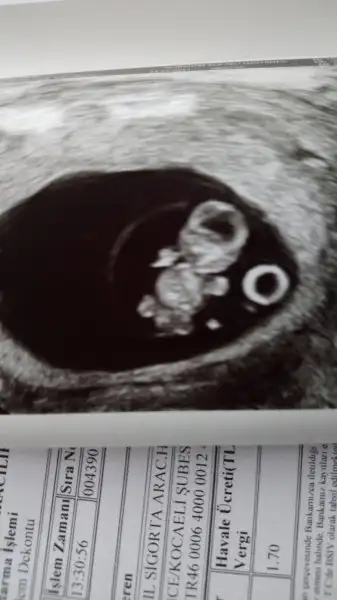

Selam kızlar bende bugün doktora gittim önden gidiyoruz 8+5 deyim. Benim akıntılarım vardı. Son 2 günde kaşıntı olunca doktorum onuda kontrol etti :( mantar... neyse bebek gayet iyiymiş, hareketli de kendisi. Kollar bacaklar çıkmış :) teyzesi bir cinsiyet yorumu da biz alalım. Mantar için bakılınca ultrasonumda vajinal oldu. interiorarchitect interiorarchitect

Selam kızlar bende bugün doktora gittim önden gidiyoruz 8+5 deyim. Benim akıntılarım vardı. Son 2 günde kaşıntı olunca doktorum onuda kontrol etti :KK43: mantar... neyse bebek gayet iyiymiş, hareketli de kendisi. Kollar bacaklar çıkmış :) teyzesi bir cinsiyet yorumu da biz alalım. Mantar için bakılınca ultrasonumda vajinal oldu. interiorarchitect interiorarchitect

Maşallah maşallah kuzuya nasıl belirginleşmiş vücudu kafası :) demekki 8. hafta da netleşiyor, ultrason görüntüsü de çok güzel. Allah esirgesin sağlıkla doğsun inşallah canım :)